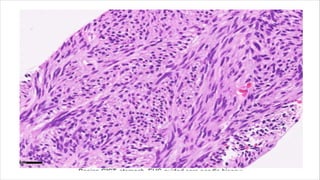

Sclerosing epithelioid fibrosarcoma

• Diagnostically problematic.

• Most commonly presents as a mass in deep soft tissue in lower

extremities.

• Other sites:- upper extremities, trunk, head & neck regions.

• Age at diagnosis45 years of age.

• Characterised by local recurrences and distant metastases.

• Well circumscribed and lobulated neoplasm with myxoid changes

or calcification.

• Infiltrative in nature.

MICROSCOPY

• Large or polygonal with eosinophilic granular cytoplasm

• Often with prominent nucleoli

• Nuclear pleomorphism including multinucleation and with rare

mitoses.

• Arranged into nests or cords and embedded into hyalinized

stroma.

• Spindled cells with varying amounts of hyalinized and myxoid

• Arcuate vessels and hyalinized collagen rosettes seen.

Immunochemistry:-

• Positive for low grade fibromyxoid stroma.

• EMA positive, cytokeratin, S100, SMA, desmin and CD34 stains are

negative.